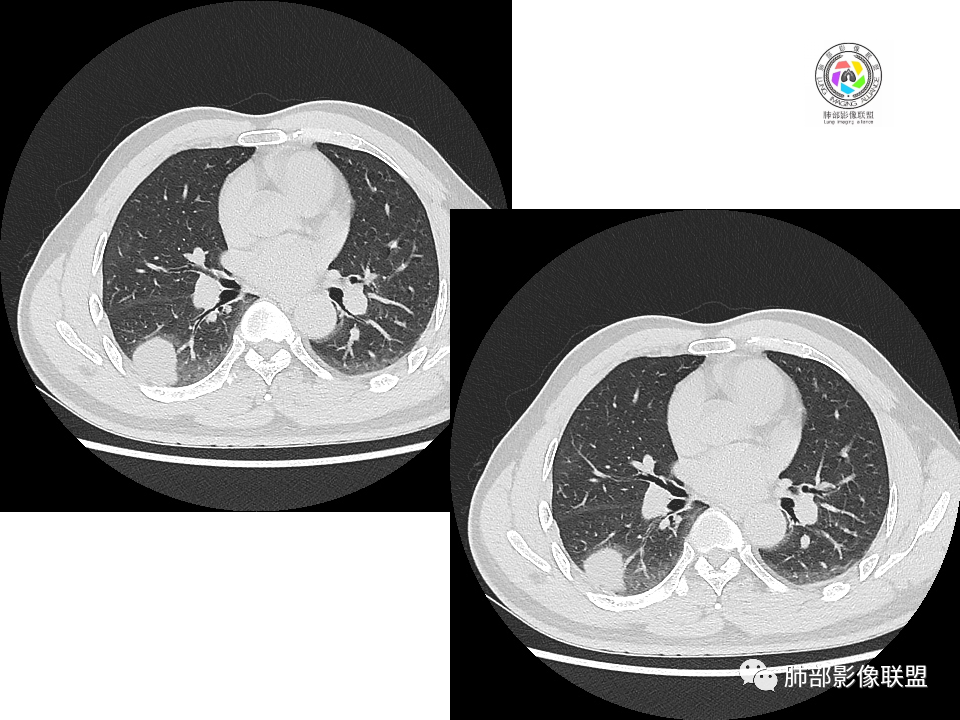

2.右肺下叶背段胸膜下块影,边界清楚光整,上下极见磨玻璃晕,未见明显分叶毛刺和棘状突起,未见胸膜凹陷或胸壁侵入。密度均匀,轻度不均匀强化。未见支气管进入。

3.右肺中叶外侧段胸膜下散在小片影,磨玻璃密度为主,边界不清,支气管相关。符合炎性特征!

4.右肺下叶基底段支气管血管束旁小结节影,边界清楚,强化不明显。注意,这结节在“遥远的”基底段。

有老师分析,多发病灶有磨玻璃晕,可以符合隐球菌感染,确实如此。但背段边缘如此锐利的块影还是更容易让人联想到新生物。

1、普通人隐球菌感染的时相:初期的隐球菌感染周围有晕,晕从多变少,或包裹,或吸收,结节实性区可迅速变大。后期(慢性期)的隐球菌周围无明显晕征,边界较清楚。

5、周围毛刺纤维、边缘形态等:坏死包裹会使得结节变圆;结节多缺乏明显的分叶征,缺乏局部突出生长能力;如果出现分叶,是由多处肉芽肿中心形成。没有坏死的局限化,结节只是凑合在一起,常呈方形征;毛刺进入晕区(概念源自南边老师),毛刺较短、较软;周围的晕吸收后,会留下不规则边,外面常残留丝状条索;收缩力较弱,临近胸膜对胸膜牵拉不明显。